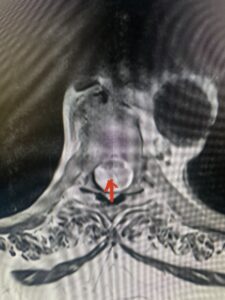

Fig 4A. Axial T2 weighted MRIs demonstrating large C5-6 herniated disc with spinal cord compression (red-arrow)

This 36-year-old female who had a long history of neck pain had a history on MRI of a C5-6 bulge. She recently after diving into a pool (not hitting her head on bottom) developed progressive problems with her arms. She had developed spontaneous shocks going down her arms and in the back of her neck. Spontaneous shocks going down the neck and spine is called a Lhermitte’s phenomenon and can occur with spinal cord compression and also with multiple sclerosis. On examination, the patient had long tract weakness of her arms, right greater than left. Her finger extensor weakness was profound on the right. MRI (Fig. 4) of the cervical spine revealed a massive C5-6-disc herniation causing significant cord compression right greater than left with subtle cord signal change. Because of the severe myelopathy, the patient was indicated for surgery. A C5-6 anterior cervical discectomy and fusion was performed (Fig. 5). The patient had a dramatic improvement of her strength in the recovery room.